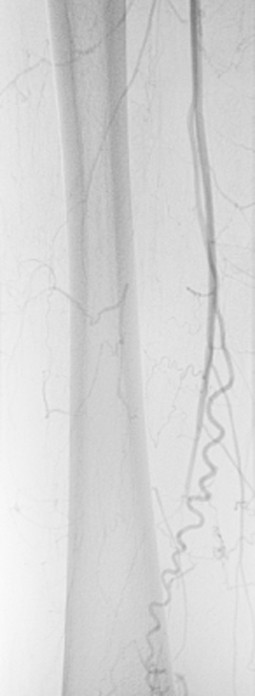

Deutsch Auch Morbus WiniwarterBuerger oder WiniwarterBuergerSyndrom Endangiitis obliterans Krankheit Medium hochladen Wikipedia Ist ein(e) Krankheit, designated intractable/rare diseases Unterklasse von arterial occlusive disease, predominantly mediumvessel vasculitis, secondary glomerular disease Benannt nach. Ischämie» die Differentialdiagnose eines Morbus WiniwarterBuerger erwogen Die selektive Angiographie vom zeigte die typischen «KorkenzieherKollateralen» am rechten Unterschenkel (Abb 1 x) Eine Ilomedintherapie war allerdings nicht erfolgreich, so dass am 1302 eine Grosszehenamputation rechts durchgeführt werden musste. Synonyme Morbus WiniwarterBuerger, VonWiniwarterBuergerKrankheit, Endarteriitis obliterans, Thrombangiitis obliterans Englisch endangitis obliterans, Buerger's disease Inhaltsverzeichnis.

Buerger related the cellular nature of arterial thrombosis, as had von Winiwarter, and described the absence of large vessel involvement It was Buerger who named the disorder “thromboangiitis obliterans”, and only briefly mentioned its relationship with smoking In 1924, Buerger reported that tobacco use was probably a predisposing factor 2. Morbus WiniwarterBuerger Stuttgart, Germany Georg Thieme;. Ischämie» die Differentialdiagnose eines Morbus WiniwarterBuerger erwogen Die selektive Angiographie vom zeigte die typischen «KorkenzieherKollateralen» am rechten Unterschenkel (Abb 1 x) Eine Ilomedintherapie war allerdings nicht erfolgreich, so dass am 1302 eine Grosszehenamputation rechts durchgeführt werden musste.